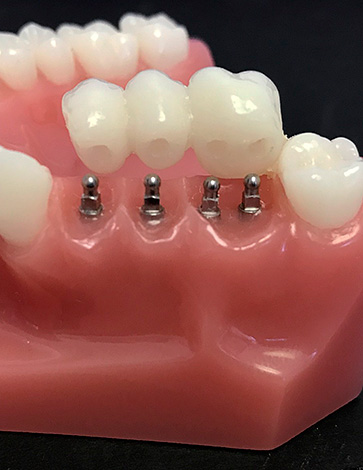

Os mini-implantes são, de fato, uma versão menor dos implantes padrão usados para fixar dentaduras e (menos comumente) pequenas pontes fixas.

Externamente, os mini-implantes são um pouco semelhantes aos implantes clássicos, mas têm um diâmetro significativamente menor. O diâmetro padrão da rosca é de 1,8-2,4 mm, devido ao qual sua introdução no osso é menos traumática e a instalação como um todo é muito mais rápida - isso é semelhante a aparafusar um parafuso autorroscante no osso (a parte inferior com a rosca é parafusada no osso, e a prótese é anexada à superior). Dependendo do tipo e formato do pilar, todos os projetos diferem tanto no campo de sua aplicação quanto em durabilidade, versatilidade e, portanto, preço.

Como observado acima, os mini-implantes costumam ser usados para fixar próteses removíveis. Dependendo do tamanho da prótese, um número diferente de implantes pode ser instalado na mandíbula, na qual uma única prótese é então acoplada. Isso proporciona uma fixação rígida da prótese, sua imobilidade ao comer e conversar e, mais importante, o conforto geral do uso. Ao mesmo tempo, a prótese em si pode ser removida e instalada nos implantes várias vezes e, ao usar alguns tipos de pilares, um número ilimitado de vezes.

Também é possível instalar pontes fixas em mini-implantes. Esse design é muito menos confiável do que ele, fixado em implantes clássicos, mas em alguns casos não possui alternativas. Por exemplo, se o processo alveolar da mandíbula inferior for muito fino para implantes comuns e o paciente não puder realizar enxertia óssea para expandir o osso por um motivo ou outro.